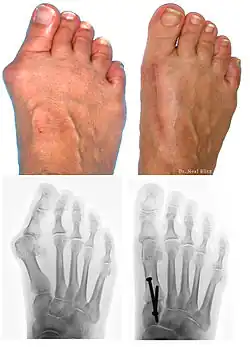

L’hallux valgus (HV, du latin hallus, gros orteil et valgus : « tourné en dehors »), souvent accompagné d'un « oignon » (callosité de la peau en regard de la déformation), est une déformation du pied correspondant à la déviation du premier métatarsien en varus (en dedans) et du gros orteil (hallux) en valgus (en dehors).

Bilan radiographique

Le diagnostic est avant tout clinique, mais des radiographies sont indispensables pour mesurer la déformation et adapter la technique chirurgicale aux spécificités du patient. Les radiographies doivent être effectuées de façon rigoureuse : clichés d'avant-pied de face, profil, et 3/4, patient debout en charge. Ce dernier critère est indispensable car le squelette du pied adopte des positions dans l'espace qui diffèrent selon que le poids du corps repose ou non sur lui. C'est l'état du squelette debout en charge qui doit guider le geste chirurgical.

Techniques opératoires

Au cours d'une intervention chirurgicale, plusieurs types de corrections peuvent être apportées, isolément ou de manière combinée :

- ostéotomie métatarsienne (« chevron » simple, ostéotomie de Scarf, etc.) ;